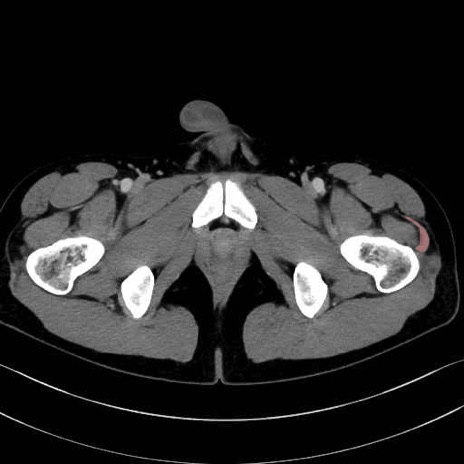

中殿筋(gluteus medius)のCT画像の解剖

中殿筋 (Gluteus medius)